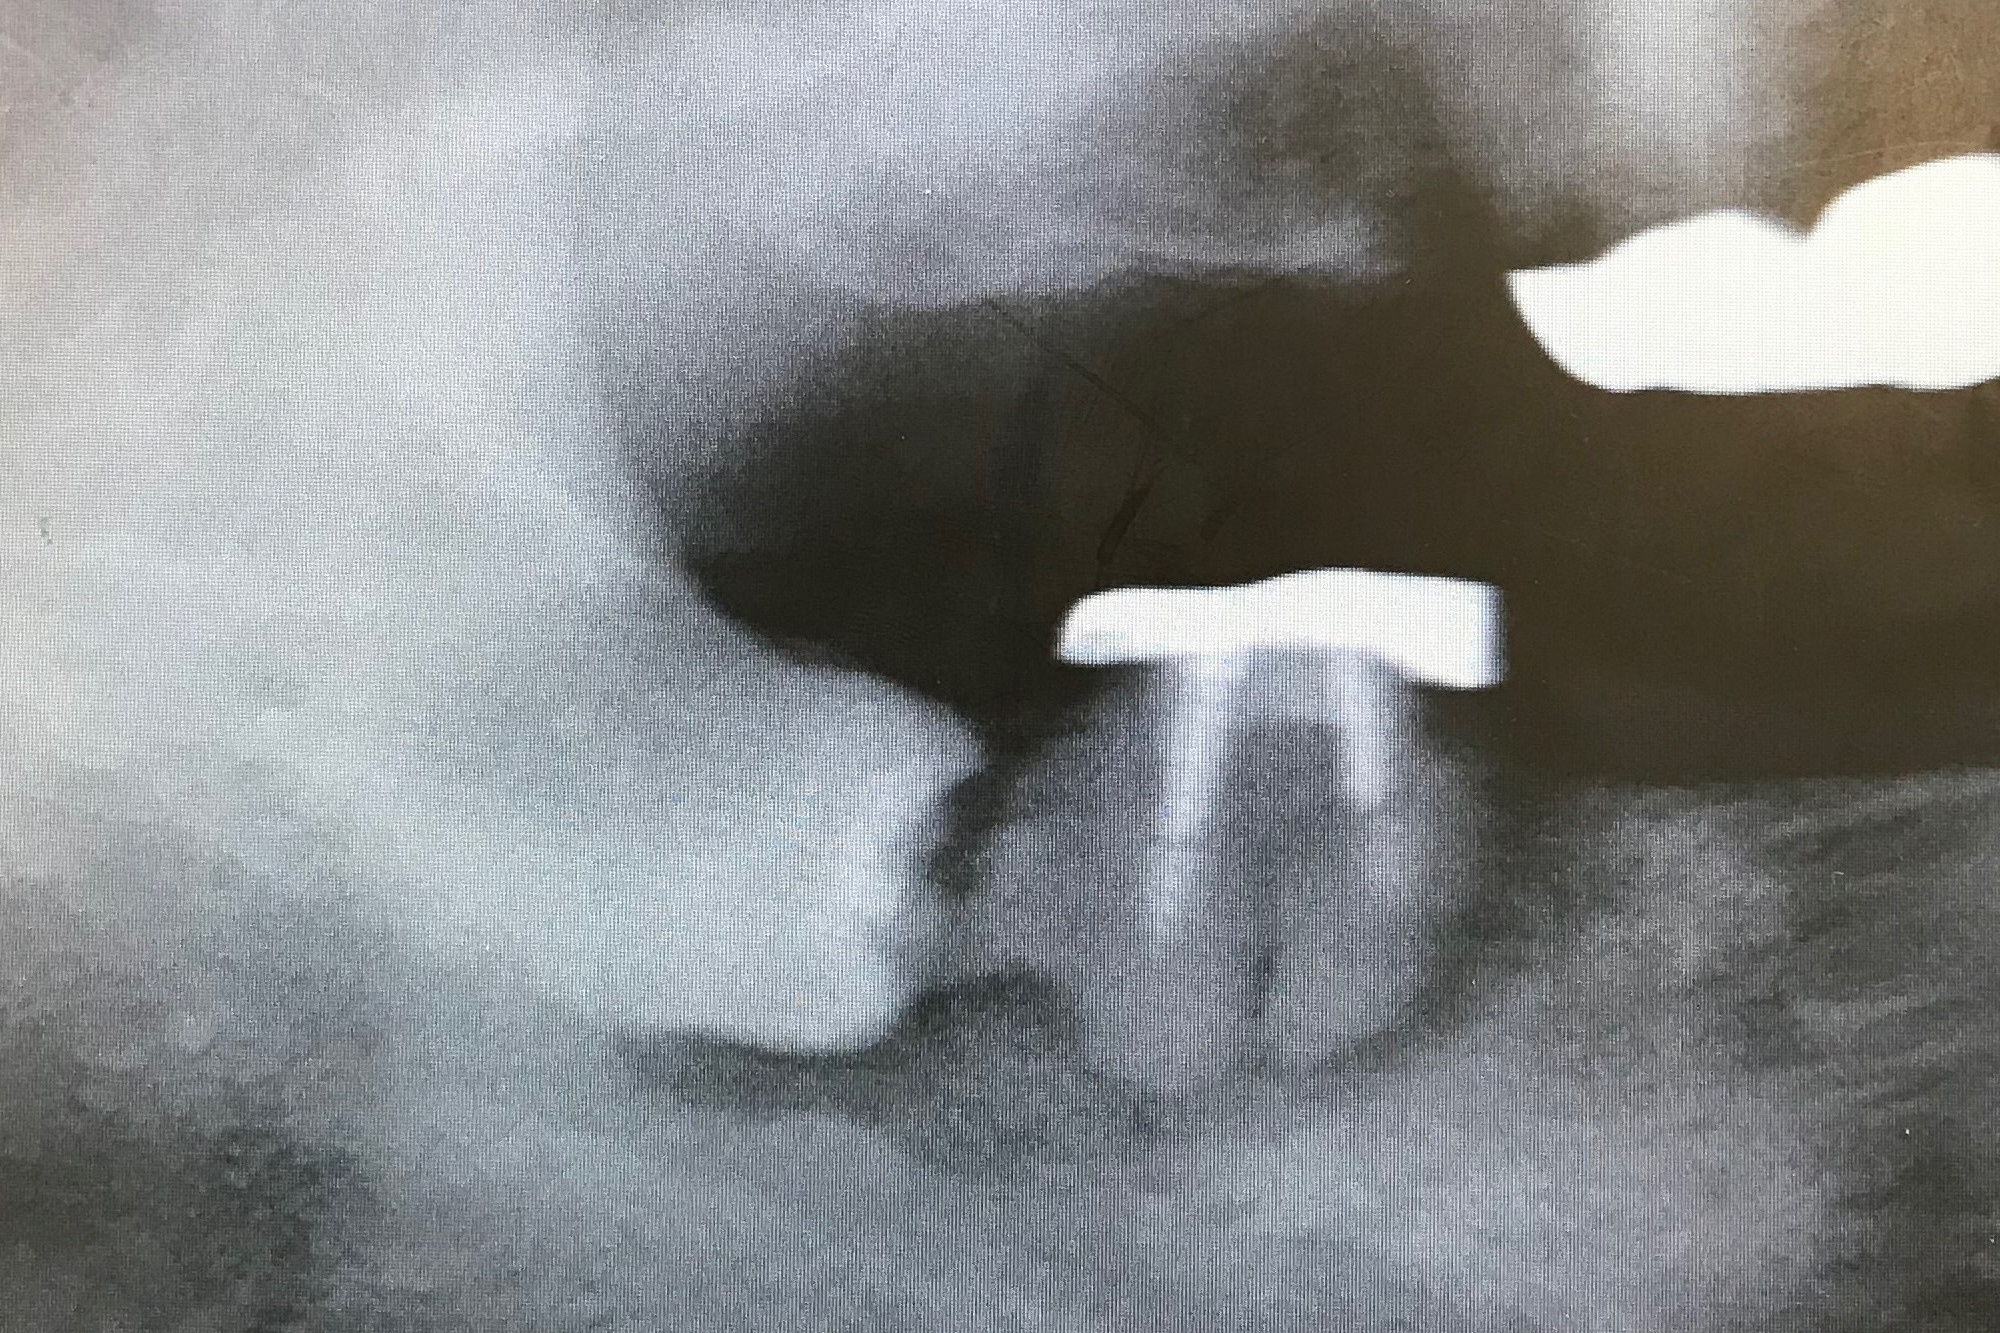

☆☆☆☆☆

おや,簡単そうな上の親知らずですね....と思うなかれ.実は虫歯が深くて,道具をかけるとボロボロと崩れてしまいます.

抜けた歯です.歯の頭が折れてしまい根っこだけ骨の中に残ってしまいました.歯茎をたくさん切って骨を削り飛ばして,ようやく抜けました.上顎洞も近いし,大変です.

抜歯した歯とレントゲンを重ねると,こんな感じになります.処置は30分もかかりました.虫歯が無ければ...1分もかかりません.みなさま,お願いです.抜歯は早めに決心してください.お互いハードモード突入してしまいます.